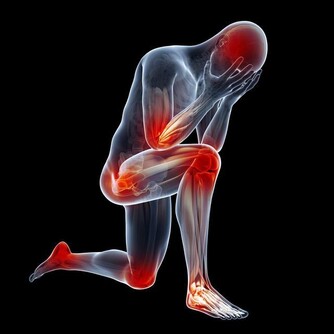

腎臟不好的8個信號

沒勁兒

腎功能一旦出現問題,身體代謝產生的廢物就難以從尿液裡排泄到體外,這時就會出現精神萎靡,疲勞、乏力等感覺。

腰痛

腎臟位於腰部的脊柱兩側,因此當腎臟出現問題時,常會感到腰痛。

水腫

飲水太多,或者是睡眠時間過長、過於肥胖等,眼瞼、臉部、小腿等部位可以出現輕微的水腫,或者一過性的水腫。但如果不是這些原因引起的水腫,就要懷疑是不是腎臟出了問題。

貧血

腎臟除了有排泄廢物等功能外,還可以分泌造血激素。當腎功能損害時,也會引起貧血。